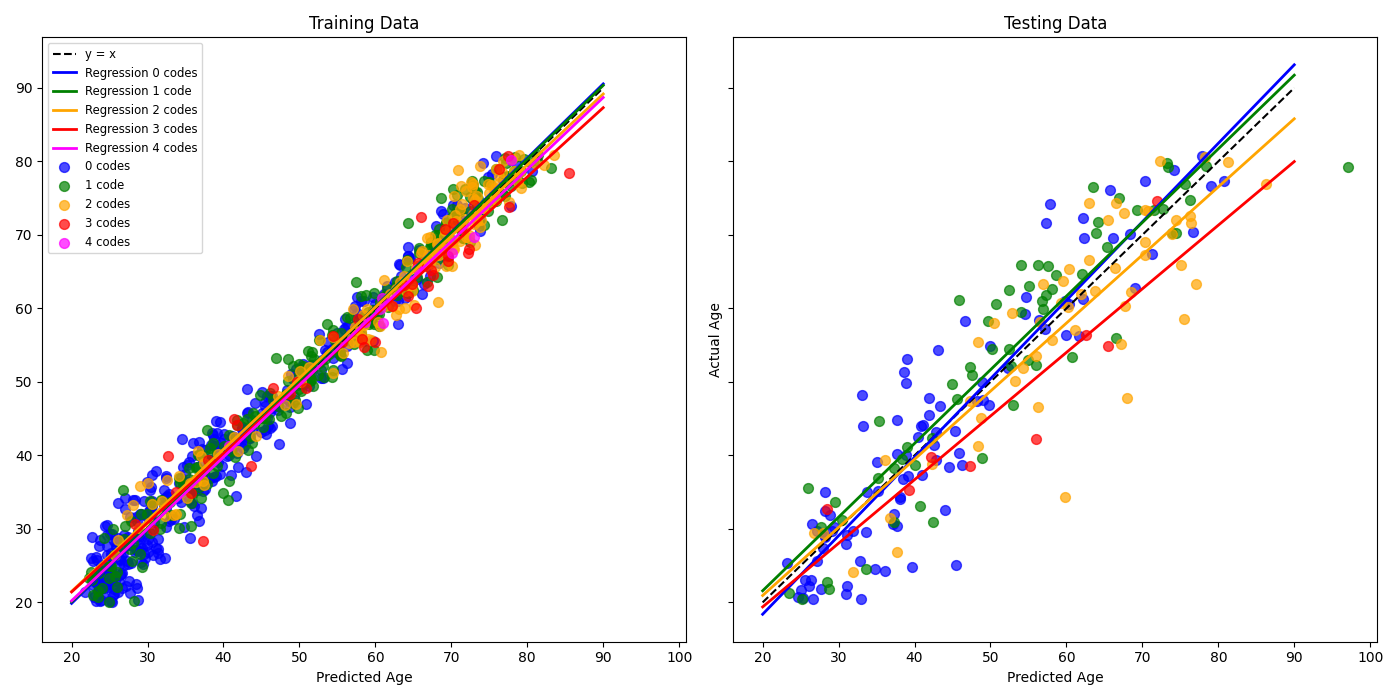

As detailed in Table 4, four ensemble types were evaluated, assuming no interaction terms and using the CNN models outlined in Figure 4. The third-order polynomial was selected as the final model due to its favorable metrics and lower variability across cross-validation splits. While the fourth-order model also demonstrated strong performance, it did not provide a substantial improvement over the third-order model and was therefore excluded to favor a less complex design.

3.2 Residual Analysis

An analysis of the residuals is the natural next step to assess the potential of a BARB using this model, which not only relies on different architecture but also different data. Figure 6 depicts the plot of real and predicted ages. The plot demonstrates strong alignment along the diagonal, indicating a high degree of accuracy in the model’s predictions. The variability is minimal and relatively uniform, suggesting that the model effectively captures underlying patterns in the data. Very mild evidence of overfitting exists as the test set exhibits greater variability in residual values compared to the training set. Overall, these plots lend credibility to the brain age model constructed here.

Although the dataset lacks granularity and may be inconsistent with labels of these five disease states, which confounds direct prediction of the specific ICD codes and produces conflicting results with ANOVA tests, we can still assess if there is a correspondence with the model residual and the disease states. Since labeling inconsistencies and misclassification are assumed to occur randomly across the dataset, any systematic relationship between negative residuals—-where the predicted brain age exceeds the chronological age—-and the presence of ICD codes would provide evidence of a meaningful correlation. Figure 7 captures exactly this. When organizing subjects in the training set by how many ICD codes are associated to them, we see each group’s trend line to be distinct (). This means that given an actual age and the number of ICD codes, the predicted age will change. In particular, those with two or more trend toward an older brain age.

The direct analysis of the training residuals grouped by number of ICD codes provided in Table 6 reveals distinct patterns across groups. Mean residuals show a slight shift from positive values (younger predicted brain ages) for individuals with no ICD codes to negative values (older predicted brain ages) for those with higher ICD counts. Median residuals follow a similar trend, reinforcing this observation. Skewness values are near zero for most groups, suggesting generally symmetric residual distributions, with slight positive skewness observed for individuals with zero or one ICD code. In other words, these two groups exhibit a tail on the positive side (associated with younger predicted brain ages). Groups with two ICD codes exhibit moderate positive skewness, reflecting a greater likelihood of outliers of those with younger predicted brain ages. Kurtosis values reveal that individuals with one or two ICD codes have heavier-tailed distributions, while those with zero, three, or four ICD codes show flatter, more normal-like distributions. These findings suggest a nuanced relationship between predicted brain age residuals and the number of ICD codes, where residual variability may increase with the presences of 1 or 2 ICD codes. Still, the trends toward an older predicted brain age is evident, mirroring the trend lines seen in Figure 7.

The analysis indicates that the number of ICD codes influences the residuals, yet attempts to model the reverse direction—predicting the number of ICD codes based on patient age and residuals—were unsuccessful. The signal-to-noise ratio appears insufficient, suggesting that numerous unobserved factors impact the ICD codes, making prediction unreliable with the available features. Among the models tested, decision trees consistently split the dataset at an actual age of approximately 48 or 49, depending on the data representation. This split is supported by Figure 6, which reveals a sharp decline in the proportion of subjects with zero ICD codes after this age threshold.

Statistical analysis corroborates this observation. A one-way ANOVA test of residuals grouped by the number of ICD codes did not yield statistically significant differences across the groups (). However, restricting the analysis to subjects older than 49 revealed significant differences (). Further exploration of this age-based split, as shown in Figure 8, highlights that residual means are positive (indicating a younger predicted brain age) for subjects aged 49 or younger, regardless of the specific ICD code. Notably, SAD exhibits the highest mean residual within this subgroup, though this result may be a statistical artifact due to the small sample size. Conversely, for subjects older than 49, residual means generally become negative, except for those with no associated ICD codes or those with HTN.